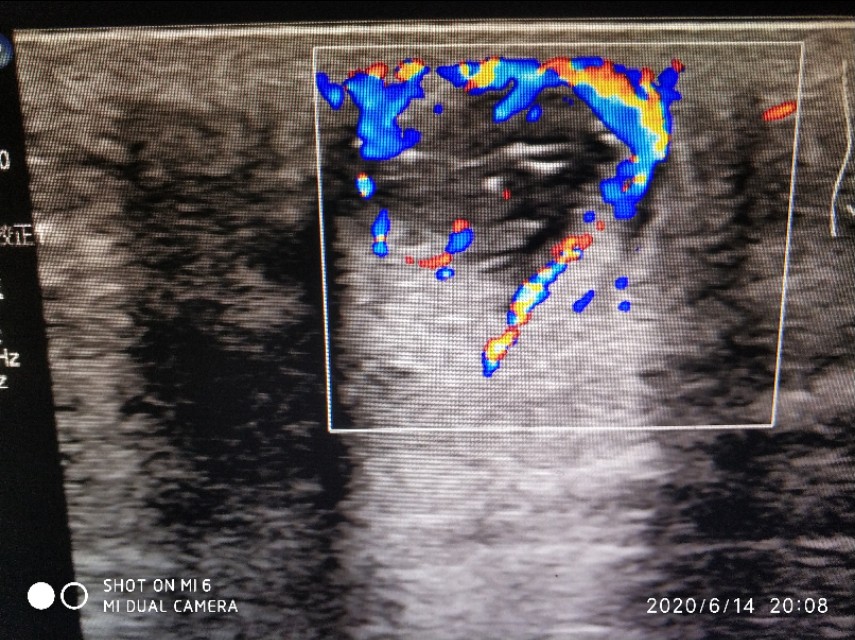

这是我们科长做的,可以看到包块周围血流还是挺丰富的,提示可能有肉芽组织增生,里面有几根条带状的毛发回声。